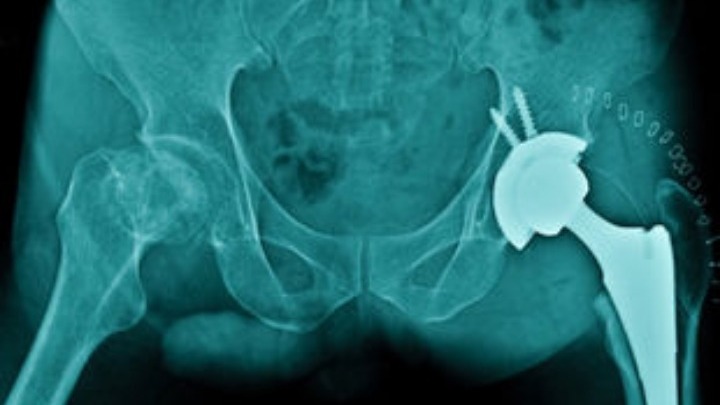

Η αρθρίτιδα του ισχίου αποτελεί μία αναπηρική κατάσταση που προκαλεί πόνο και δυσκαμψία στην άρθρωση του ισχίου και η πιο σημαντική ίσως επέμβαση η οποία βελτιώνει την ποιότητα ζωής των ασθενών είναι η αρθροπλαστική, τονίζει ο Σπύρος Δαρμανής, Ορθοπαιδικός Χειρουργός στο 401 στρατιωτικό νοσοκομείο. Εξηγεί ότι η αρθροπλαστική είναι η μέθοδος όπου η κεφαλή του μηριαίου οστού η οποία έχει υποστεί φθορά και η αντίστοιχη υποδοχή της πυέλου (κοτύλη) αντικαθίστανται με εμφυτεύματα τα οποία εξασφαλίζουν καλή λειτουργία της άρθρωσης χωρίς πόνο.

Ο κ. Δαρμανής αναφέρει «ότι υπάρχει αυτή τη στιγμή στην Ελλάδα η αρθροπλαστική του ισχίου τύπου Exeter (από το Exeter της Μ. Βρετανίας), της οποίας η αντοχή στο χρόνο αγγίζει τα… σαράντα χρόνια». Ειδικότερα, σύμφωνα με τον κ. Δαρμανή στη διεθνή επιστημονική βιβλιογραφία μελετήθηκε η επιβίωση της μηριαίας πρόθεσης- από την εγχείρηση που το εμφύτευα λειτουργεί άψογα και μετρήθηκε έπειτα από πόσα χρόνια η πρόθεση αυτή (εμφύτευμα) «χαλαρώνει» και φυσικά απαιτείται επανεγχείρηση. Η συγκεκριμένη ανάλυση απέδειξε ότι στα 33 χρόνια μετά την εμφύτευση η επιβίωση είναι 91%. Αυτό σημαίνει, αναφέρει ο κ.Δαρμανής, ότι το 91% των χειρουργημένων ασθενών στα 33 έτη μετά την αρχική επέμβαση έχει μηριαία πρόθεση που λειτουργεί άριστα. «Σε καμία περίπτωση δεν σημαίνει ότι μόνο αυτή η πρόθεση μπορεί να έχει άριστα αποτελέσματα, απλώς ότι αυτή η πρόθεση το έχει αποδείξει», τονίζει ο κ. Δαρμανής.